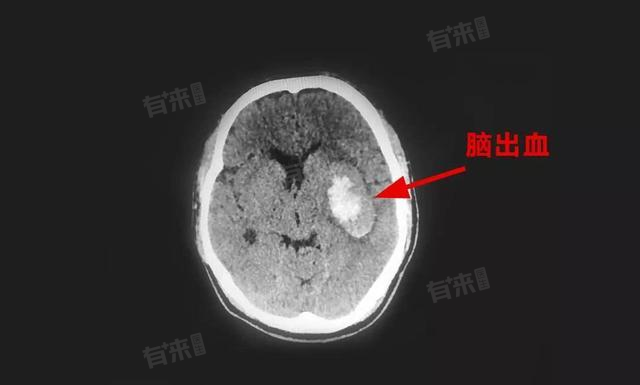

脑出血的出血量通常是通过CT(计算机断层扫描)片子来进行计算的,这种方法存在一定的误差,且需要结合患者的临床信息来综合评估病情。在诊断和治疗过程中,应始终遵循专业医生的指导。

- 在CT片子上,先确定血肿的最大长度(L)、最大宽度(W)以及最大厚度或层数(H),注意这里可能需要将血肿模拟为多层结构,每层厚度由CT扫描的层厚决定。这些尺寸通常是通过在CT图像上直接测量得到的,可以使用CT机上的测量工具或专业的图像处理软件。

- 脑出血的大致出血量可以通过出血量=(L×W×H)/2。这个公式假设血肿是一个椭球体,虽然实际情况可能有所差异,但这种方法是目前被广泛认可的。由于CT扫描的层厚和血肿形态的不规则性,这种方法计算出的出血量可能存在一定的误差。

- 如果血肿形态比较规则,如接近椭球体,上述公式的计算结果相对准确。如果血肿形态不规则,可能需要采用更复杂的计算方法,如逐层计算并相加各层的面积来得到总体积。这种方法虽然工作量较大,但结果通常更准确。